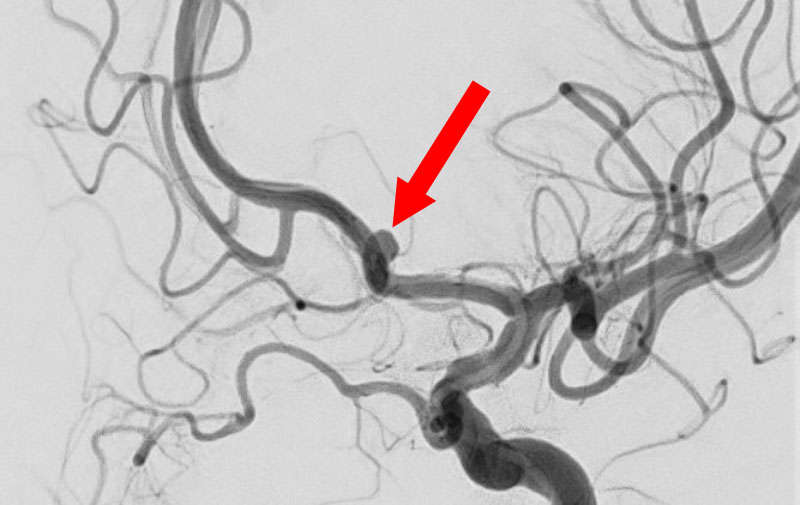

'25年10月

くも膜下出血

前交通動脈瘤破裂

40代

大阪府の病院

No.1589 手術前

No.1589 手術中

No.1589 手術後